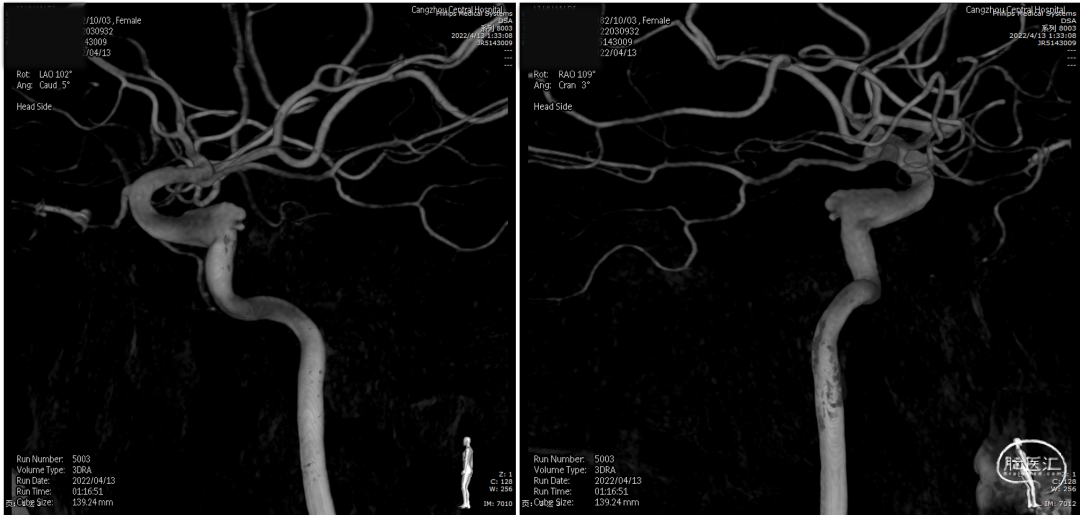

右颈内动脉3D重建(海绵窦段宽径7.2mm)

全脑血管造影

左颈内动脉3D重建图像(眼段宽径7.8mm)

左颈内动脉3D重建图像(海绵窦段宽径6.5mm)

术后复查右颈内动脉3D重建

术后3D重建

术后3D图像及透视

术前、术后3D图像对比